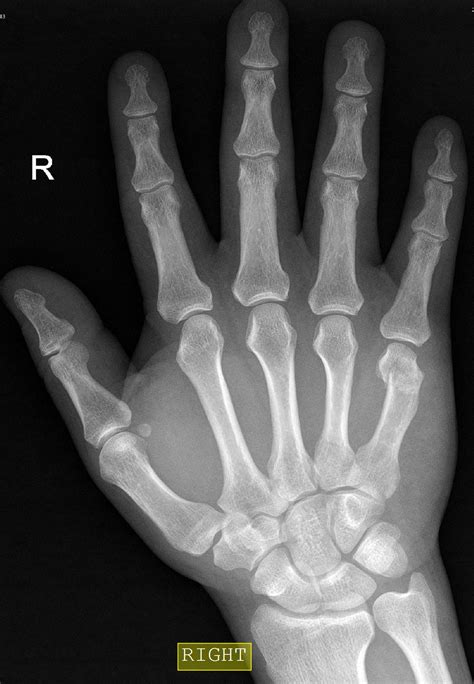

Toe Injury. Bruise And Trauma Treatment. Medical Intervention. Fracture

Toe Injury. Bruise And Trauma Treatment. Medical Intervention. Fracture ...